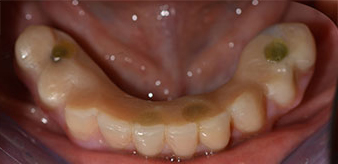

След това е взет отпечатък и е определена захапката на пациента, за да може зъботехникът незабавно да започне изработването на временната протеза. Протезата е поставена в същия ден (Фиг. 17 и 18).

След изчакване на необходимото време за осеоинтеграция, финалният отпечатък на имплантите е свален и следователно е изработена финалната протеза (Фиг. 19 и 20). В този момент, лекарят по дентална медицина и пациентът могат да обсъдят дали да използват керамични или пластмасови фасети и циркониева или метална рамка. В този случай, екипът на д-р Паску избира пластмасови фасети, имайки предвид неясната прогноза относно частичното обеззъбяване в челюстта и фактът, че зъб 24 е прорастнал. Този вид протеза обикновено е по-лесна за адаптиране и впоследствие може да бъде променяна спрямо новата ситуация в челюстта.